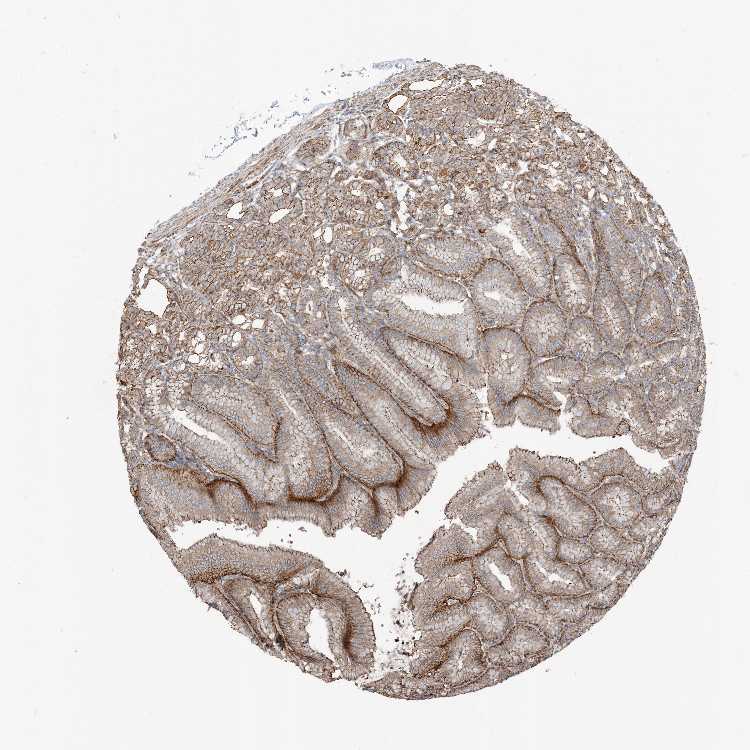

TISSUE PRIMARY DATA STOMACH Show tissue menu

STOMACH 1 - Antibody stainingi

Antibody staining in the annotated cell types in the current human tissue is reported as not detected, low, medium, or high, based on conventional immunohistochemistry profiling in selected tissues. This score is based on the combination of the staining intensity and fraction of stained cells.

Each image is clickable and will lead to virtual microscopy that enables deeper exploration of all samples and also displays staining intensity scores, fraction scores and subcellular localization as well as patient and tissue information for each sample.

Antibody HPA031833Antibody HPA031834

Glandular cells MediumMedium

STOMACH 2 - Antibody stainingi

Glandular cells HighMedium